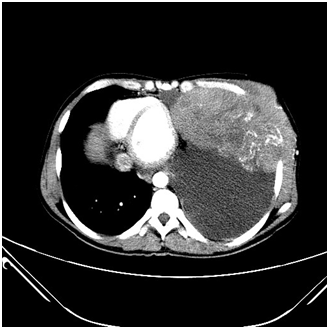

Figure 10 Contrast enhanced axial CT sections of the thorax showing a heterogenous mass arising from the chest wall.

Figure 11 Contrast enhanced axial CT sections of the thorax showing a heterogenous mass arising from the chest wall with large axillary lymph nodes.